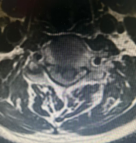

术后复查显示内固定位置良好、椎管减压充分,患者自觉症状明显缓解

为确保手术成功,骨科二区专家团队与湘雅三医院苗惊雷教授紧密协作,在麻醉科和手术室的配合下,成功为患者实施颈前路椎间盘切除术+椎管扩大减压术+植骨融合内固定术,患者术后即感四肢肌力明显改善,目前恢复良好,已顺利出院。